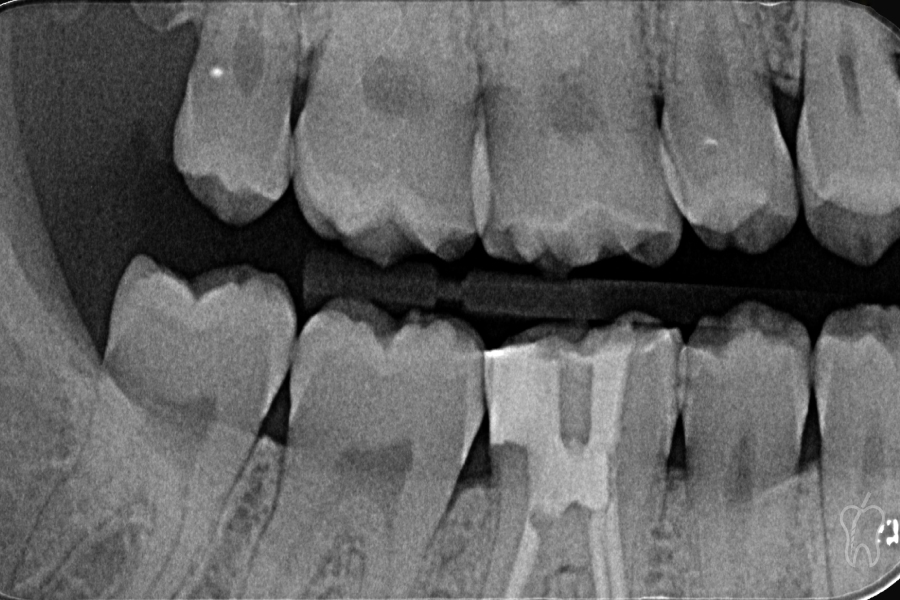

La paciente acudió a consulta refiriendo dolor agudo al frío y a los cambios de temperatura en el diente 4.6, acompañado de ligera molestia a la masticación en los últimos días (Figura 1)

Figura 1

La exploración mostró:

• Caries distal profunda proximopulpar, claramente visible radiográficamente.

• Vitalidad muy aumentada y dolorosa a las pruebas térmicas.

• Percusión ligeramente positiva, sin signos de periodontitis apical en la imagen inicial.

• Sondaje fisiológico en todo el perímetro.

• Ausencia de movilidad y sin signos de fractura o fisura.

El diagnóstico final fue:

Pulpitis irreversible sintomática sin afectación periapical.